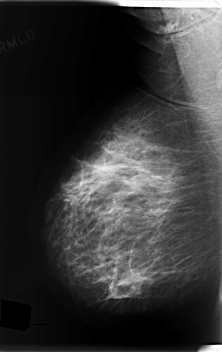

C_0203_1.LEFT_MLO

LEFT_MLO LINES 6016 PIXELS_PER_LINE 3144 BITS_PER_PIXEL 12 RESOLUTION 50 OVERLAY

FILE: C_0203_1.LEFT_MLO.OVERLAY

TOTAL_ABNORMALITIES 1

ABNORMALITY 1

LESION_TYPE CALCIFICATION TYPE PLEOMORPHIC DISTRIBUTION REGIONAL

ASSESSMENT 5

SUBTLETY 5

PATHOLOGY MALIGNANT

TOTAL_OUTLINES 1

BOUNDARY